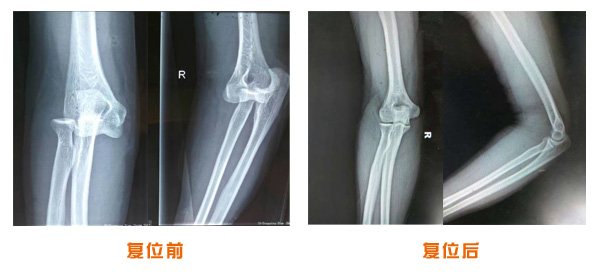

肥城市安駕莊梁氏骨科醫(yī)院是一所以梁氏手法正骨配合膏藥為特色的現(xiàn)代化專科醫(yī)院。

梁氏骨科術(shù)始創(chuàng)于清雍正年間,歷經(jīng)八代,至今已有三百年歷史。據(jù)1929年泰安縣志載“梁瑞圖先生,字增生,號(hào)蓮峰,安駕莊人,精岐黃并發(fā)明接骨,凡跌打車凡跌打車軋皮不破而碎骨者......【詳細(xì)】 |